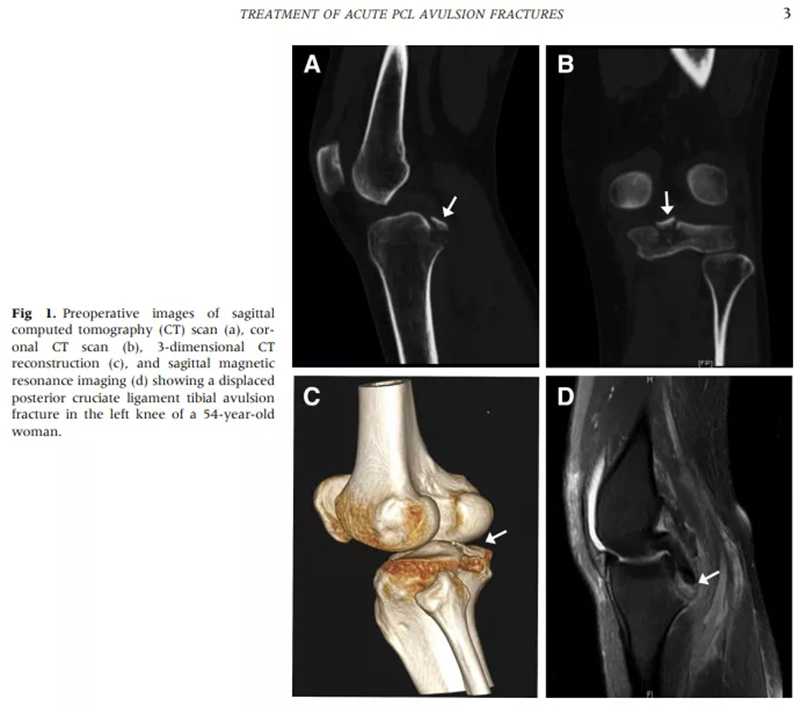

本研究旨在通過懸吊技術(shù)評估關(guān)節(jié)鏡治療急性后交叉韌帶(PCL)撕脫性骨折的臨床效果。目前,Pubmed檢索該手術(shù)類似技術(shù)國際報道僅有6篇文獻(xiàn),共計10余例病例,而我院應(yīng)用該技術(shù)已累計完成后交叉韌帶撕脫性骨折的手術(shù)40余例。

由于膝關(guān)節(jié)后方血管和神經(jīng)比較多,而且視野比較隱蔽,給關(guān)節(jié)鏡微創(chuàng)手術(shù)帶來很大的困難和挑戰(zhàn)。目前,國內(nèi)外許多大醫(yī)院仍然應(yīng)用開放手術(shù)治療該骨折。但是開放手術(shù)創(chuàng)傷大、恢復(fù)期長,而且很難避免血管神經(jīng)損傷、血腫形成、關(guān)節(jié)僵硬等風(fēng)險,不僅在治療過程中給患者帶來很大的痛苦,而且治療效果也不盡人意。國際上一直在尋求手術(shù)方式的突破,但是由于手術(shù)難度大,目前只有10余例個案報道,沒有系統(tǒng)總結(jié)和分析。

徐醫(yī)附院通過關(guān)節(jié)鏡微創(chuàng)手術(shù),只需做4個8mm左右的小切口,通過做一個直徑0.45cm、長約5cm的骨隧道,將長線環(huán)帶袢鈦板引入關(guān)節(jié)內(nèi),鈦板固定骨折,即可取得很好的穩(wěn)定性,經(jīng)過長時間大規(guī)模的病例累計,形成了40例的總結(jié)分析和評估,系統(tǒng)地講述了關(guān)節(jié)鏡下微創(chuàng)處理后交叉韌帶撕裂的手術(shù)方式、要點和治療效果,對行業(yè)發(fā)展也具有很好的借鑒意義。